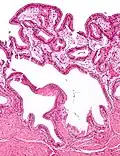

Micrografia da colesterolose da vesícula biliar.

Micrografia da colesterolose da vesícula biliar.